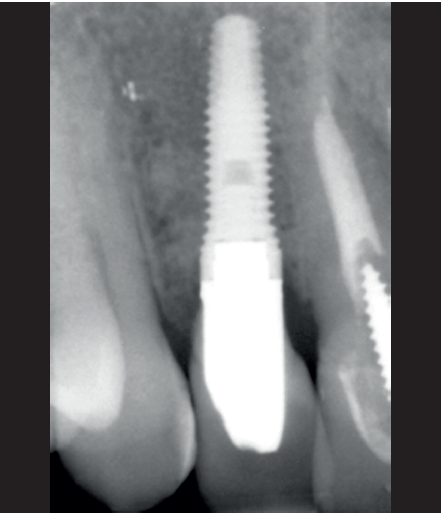

Para continuar con el estudio del caso se realiza un Cone-Beam donde poder observar tridimensional ente la posición del implante situado en posición 1.2. En los cortes seccionales se visualiza completamente situado hacia vestibular con una reabsorción casi completa de la cortical ósea de esta área, lo que explica los problemas de tejido blando subyacente. En la radiografía periapical se observa la posición del implante con respecto a los dientes adyacentes

(Figuras 5 y 6). Con esta imagen se procede a la apertura de un colgajo y la explantación del implante. Se retira también la corona situada en el diente 1.1 para poder realizar otra corona que servirá para apoyar el provisional en extensión para la zona del 1.2, mientras cicatriza la primera intervención. En este primer abordaje se coloca también un injerto en bloque obtenido de la rama mandibular que se fija con un microtornillo en la zona a regenerar donde se ha perdido la cortical vestibular. Una vez fijado y posicionado, se rellena alrededor del injerto en bloque con hueso particulado obtenido con un bone-scraper de la misma zona donante embebido en PRGF-Endoret para una mejor fijación y viabilidad celular (Figuras 7-9).